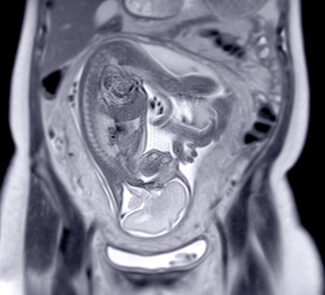

Fetal MRI: When Ultrasound Needs a Second Look

Fetal MRI supplements prenatal ultrasound by providing more explicit images of fetal anatomy and by further evaluating any abnormalities detected. There is no evidence that MRI harms the fetus, but IV contrast is avoided during pregnancy. (10)

When is fetal MRI performed?

- According to practice guidelines, performing fetal MRI before 18 weeks of gestation typically does not provide additional information compared to high-quality (often transvaginal) ultrasound imaging. MRI becomes progressively more valuable later in pregnancy, as many anatomical structures can be visualized with greater detail at advanced gestational ages. (4)

- In clinical practice, fetal MRI is most frequently performed during the second or third trimester to evaluate further findings identified on ultrasound, except when an earlier examination is urgently indicated for medical reasons. (10)

What fetal conditions are commonly evaluated?

Fetal MRI is frequently used to assess abnormalities affecting the brain, spine, chest and lungs, abdomen and pelvis, and the placenta. It serves a vital role in supporting diagnosis, informing therapeutic discussions, and facilitating delivery planning. (10)